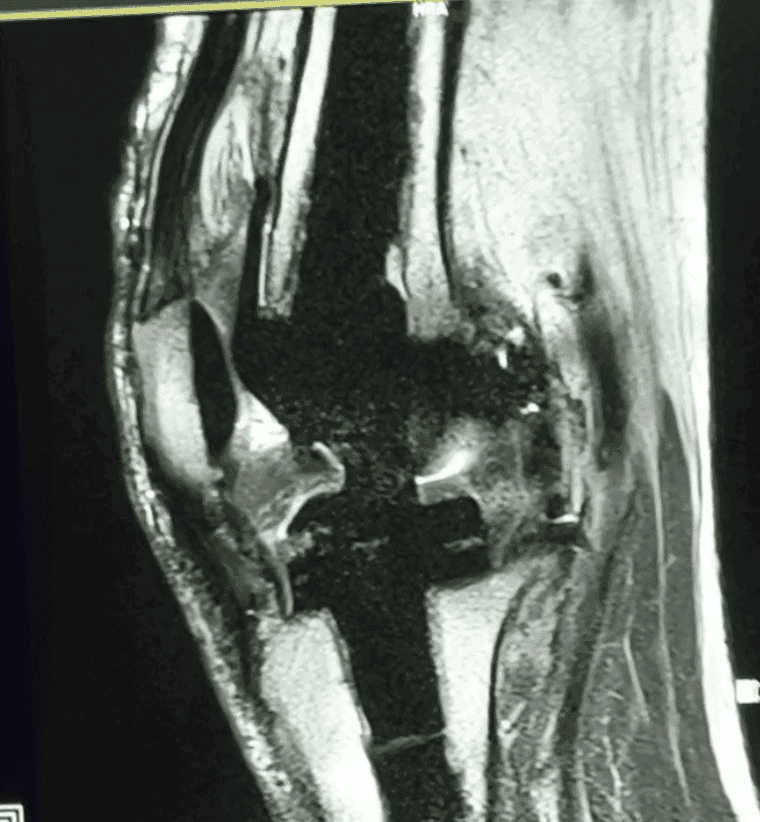

- Versatilidad: ortopedia, neurología, abdomen, pelvis y más.

MRI de alta resolución, con enfoque clínico

Nuestro objetivo es que salgas con un estudio claro, útil y confiable para tu médico. Trabajamos con protocolos optimizados para calidad 3T, y acompañamiento en cada paso.